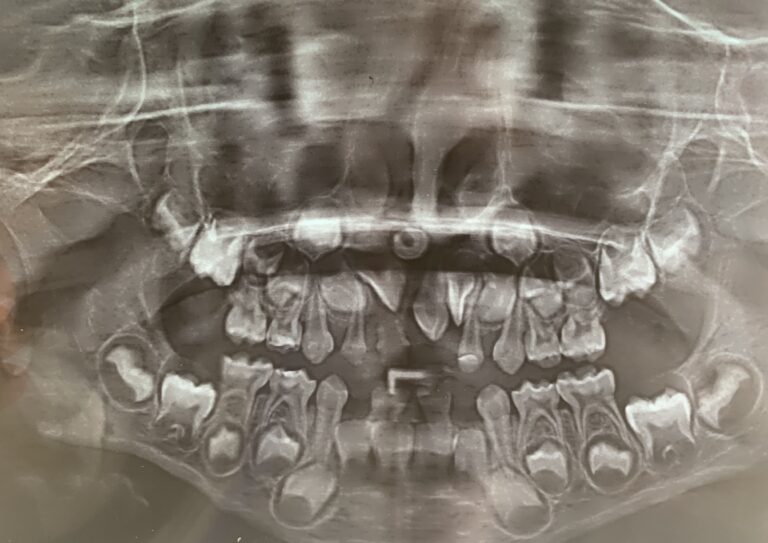

La exodoncia, comúnmente conocida como extracción dental, es un procedimiento quirúrgico que implica la remoción de un diente de su alveolo en el hueso maxilar o mandibular. Este procedimiento puede ser simple o quirúrgico, dependiendo de la ubicación y la condición del diente, por lo cual es fundamental que sea realizado por un especialista.

• Dientes impactados: Especialmente en el caso de las muelas del juicio, que no pueden erupcionar correctamente y pueden causar dolor, infección o daño a dientes adyacentes.

• Dientes supernumerarios: Dientes adicionales que impiden el alineamiento adecuado de los otros dientes.